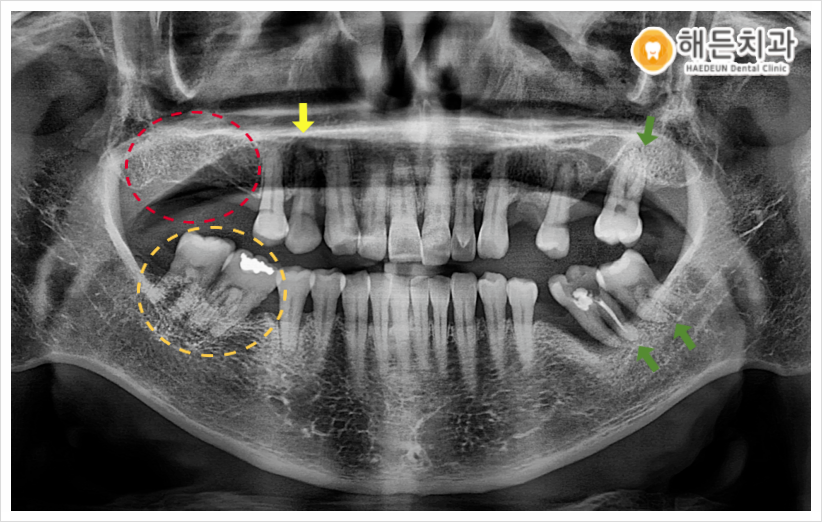

오늘 소개해 드릴 분께서는 빨간색 동그라미 표시의, 오른쪽 위턱 어금니 부위의 임플란트 치료를 원하셨는데요. 치주 질환으로 인해 잇몸 건강이 나빠지면서 어금니 치아를 상실하게 되었다고 말씀해 주셨습니다.

파노라마사진을 촬영하여 검사해 보았더니, 환자분께서 치료를 원하시는 부위를 제외하고도 문제가 있는 치아들을 다수 확인할 수 있었는데요.

✔ 노란색 화살표의 오른쪽 위턱 첫 번째 작은 어금니(#14) 주변으로 잇몸뼈가 많이 녹아 동요도가 심하여, 발치가 필요한 상황이었습니다.

✔ 그리고 주황색 동그라미의 오른쪽 아래턱 어금니 부위에는 첫 번째 큰 어금니(#46)가 상실한 상태라, 나머지 두 어금니(#47,48)가 첫 번째 큰어금니 자리로 많이 기울어져 있었으며 위에 맞물리는 어금니가 없다 보니 위로 솟구쳐 올라와 있었습니다.

✔ 또한 왼쪽 위아래 어금니 부위도 주변 치아 상실로 인해 치아가 많이 기울어져 있었으며 주변 잇몸 상태도 많이 안 좋아 동요도가 있는 상황으로, 발치가 필요한 상태였습니다.